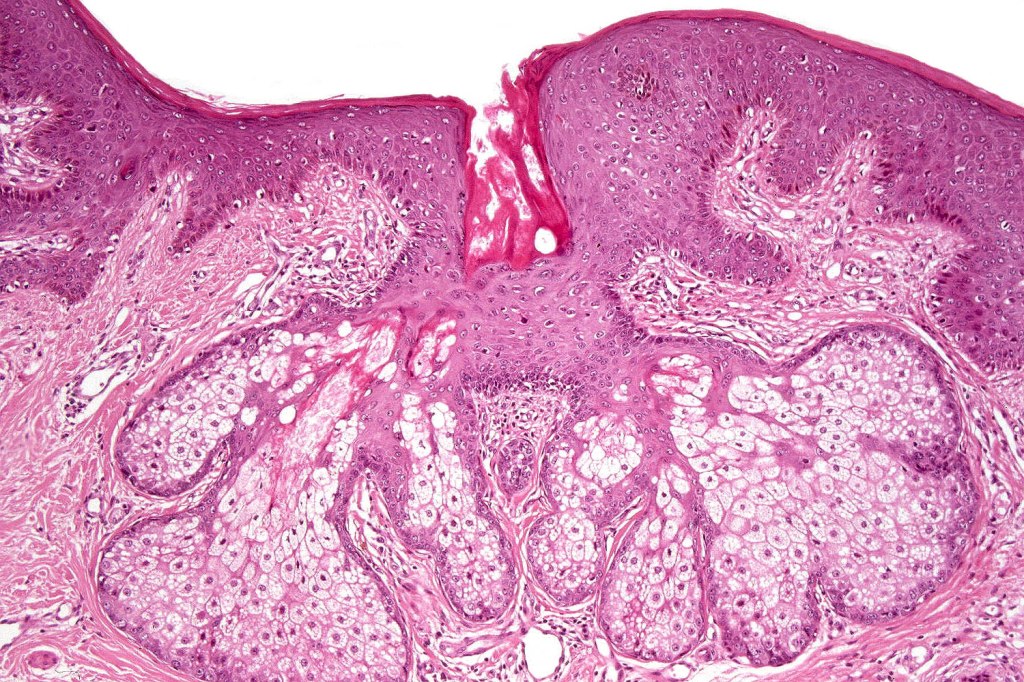

•Sharply circumscribed, unencapsulated nodule in deep dermis +/- subcutaneous fat or deeper (trichoepithelioma is much more superficial)

•Although many authors state that an epidermal origin/connection is not a feature of trichoblastoma, my own experience is that this can often be present particularly in those examples where a superficial dermal component is present in addition to the deep dermal/subcutaneous element

•Variable keratocysts